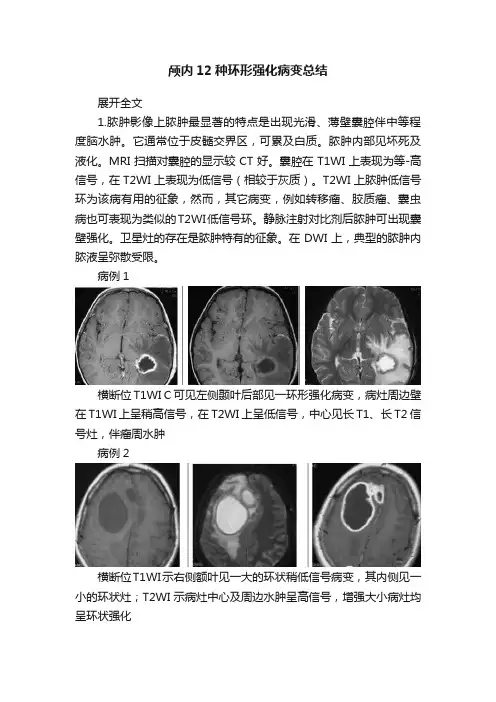

颅内12种环形强化病变总结展开全文1.脓肿影像上脓肿最显著的特点是出现光滑、薄壁囊腔伴中等程度脑水肿。

它通常位于皮髓交界区,可累及白质。

脓肿内部见坏死及液化。

MRI扫描对囊腔的显示较CT好。

囊腔在T1WI上表现为等-高信号,在T2WI上表现为低信号(相较于灰质)。

T2WI上脓肿低信号环为该病有用的征象,然而,其它病变,例如转移瘤、胶质瘤、囊虫病也可表现为类似的T2WI低信号环。

静脉注射对比剂后脓肿可出现囊壁强化。

卫星灶的存在是脓肿特有的征象。

在DWI上,典型的脓肿内脓液呈弥散受限。

病例1横断位T1WI C可见左侧颞叶后部见一环形强化病变,病灶周边壁在T1WI上呈稍高信号,在T2WI上呈低信号,中心见长T1、长T2信号灶,伴瘤周水肿病例2横断位T1WI示右侧额叶见一大的环状稍低信号病变,其内侧见一小的环状灶;T2WI示病灶中心及周边水肿呈高信号,增强大小病灶均呈环状强化病例3横断位及冠状位T1WI C图像示一环状强化灶并小卫星灶;DWI 示囊腔内呈弥散受限,ADC为低值2.星形细胞瘤(2级)星形细胞瘤II级被认为是低级别的胶质瘤。